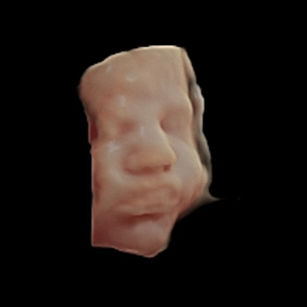

Skin: Now smooth, soft, and pink; most of the protective vernix caseosa (the creamy coating) is fading, though some may still be present at birth.

Eyes: Babies can open and close their eyes and even respond to changes in light.